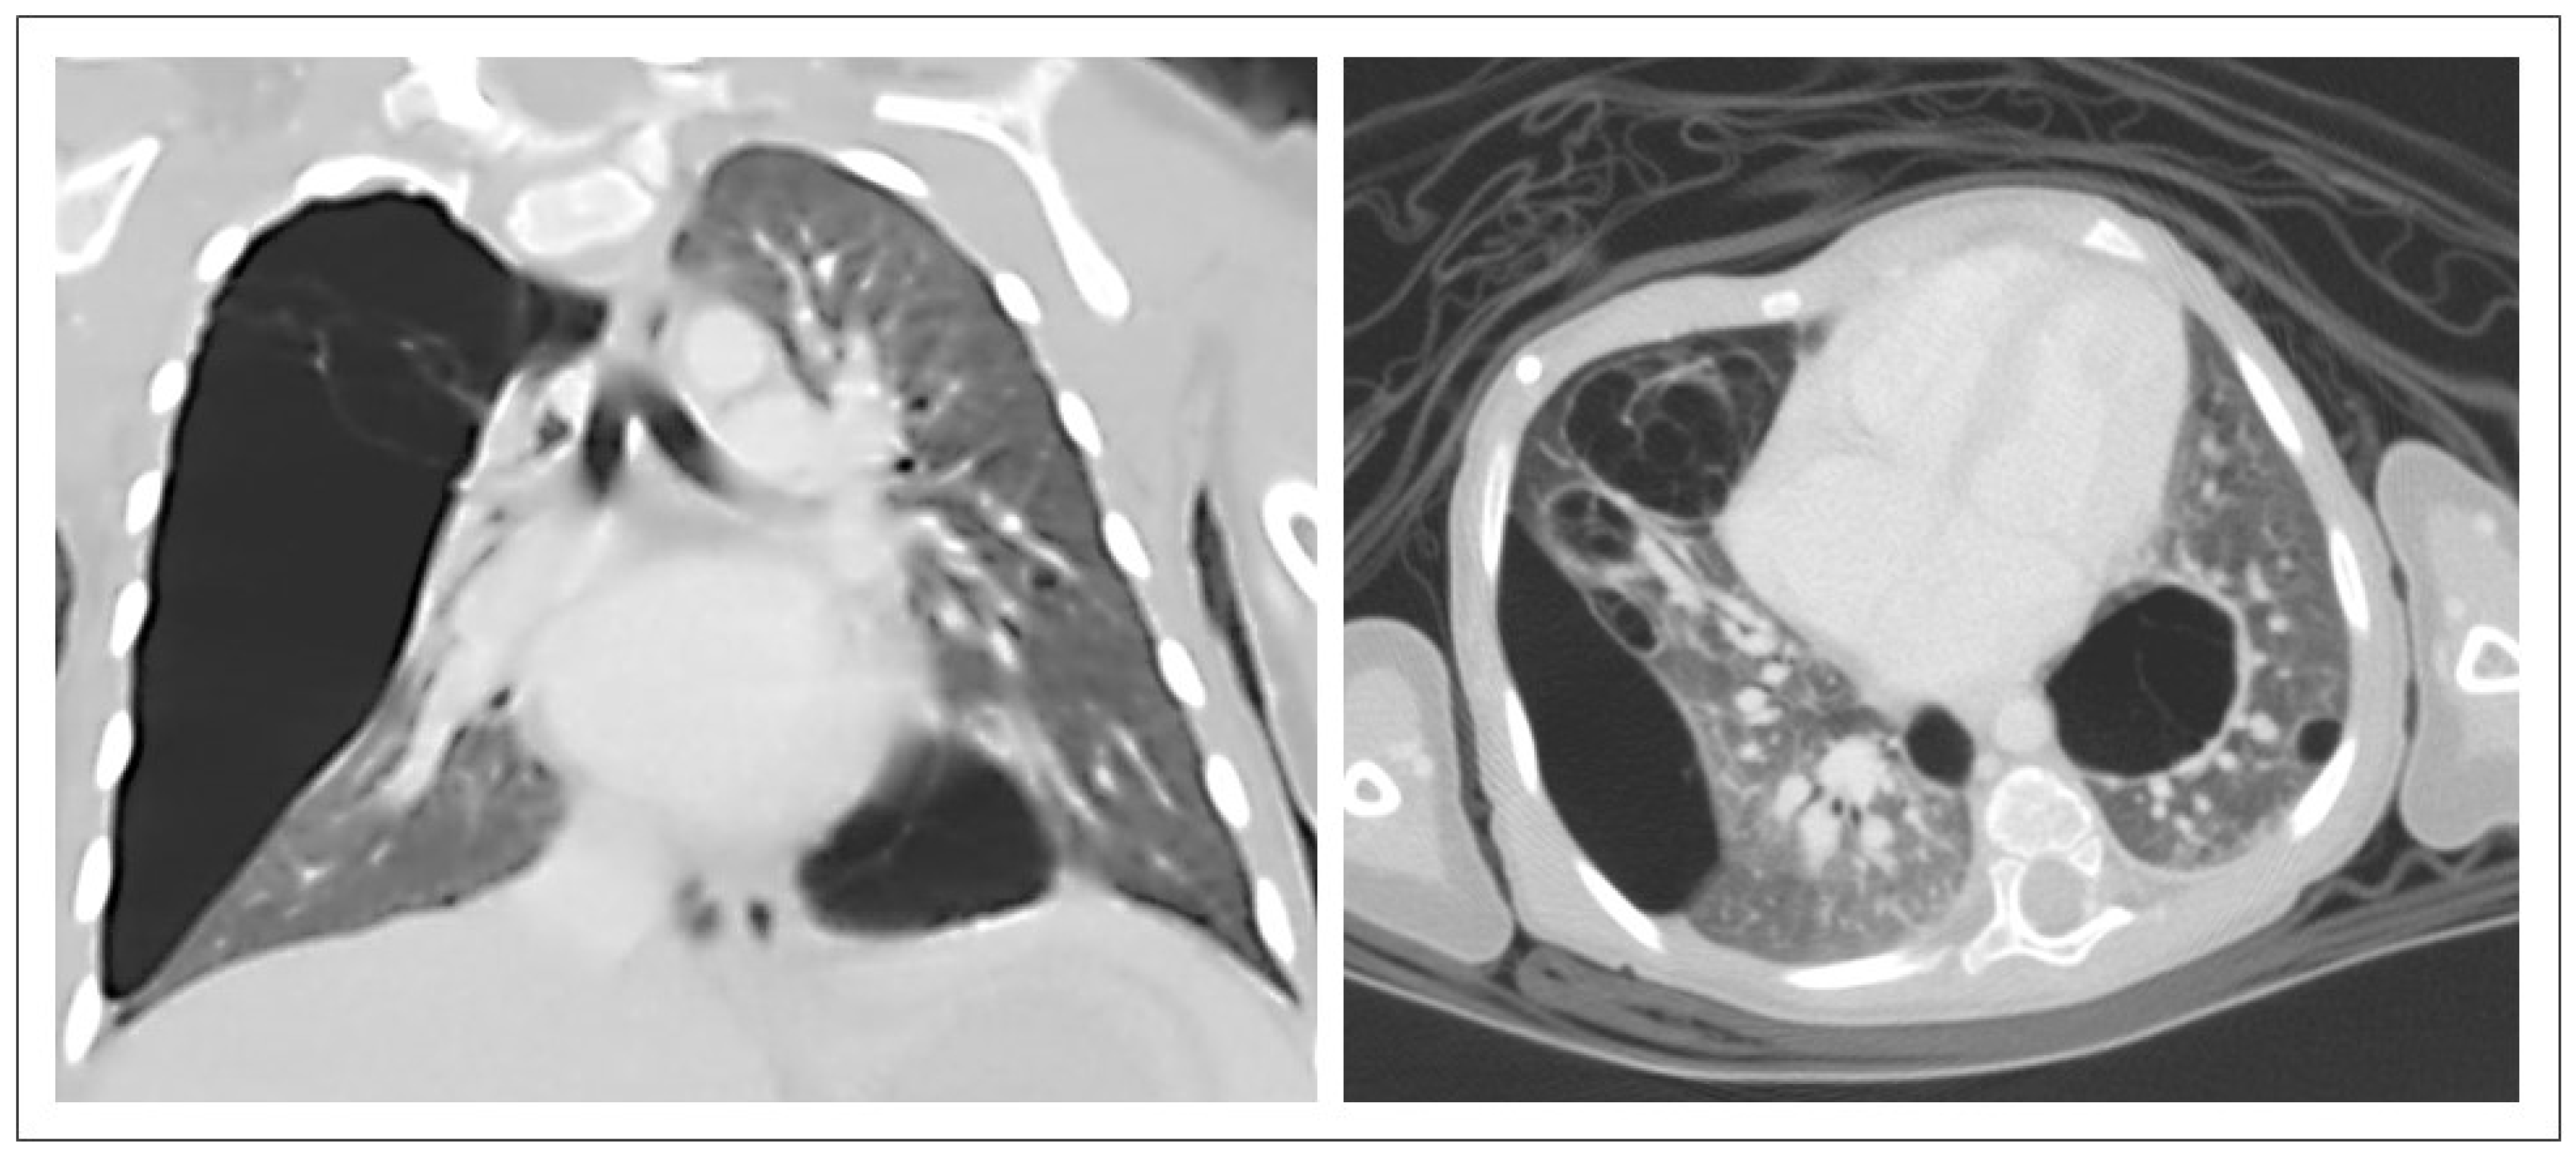

3.2. CPAM CT Findings

4.2. CPAM CT Findings